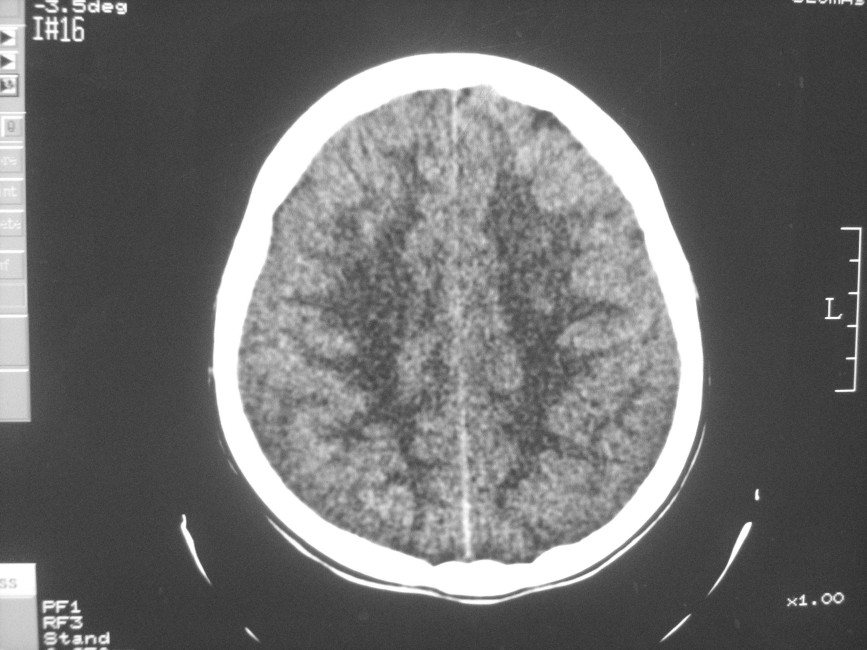

以下是引用zzyy在2008-6-16 10:13:00的发言:[br]两侧脑白质呈对称性密度减低,病儿有发热及脑膜刺激征。考虑急性病毒性脑炎。